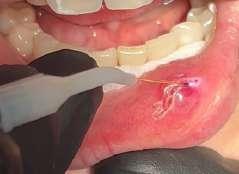

Il mucocele del cavo orale è la seconda lesione più comune. Nella fascia di età compresa tra 10 e 29 anni, il tasso di incidenza è più elevato. Il mucocele è caratterizzato da un accumulo di mucine. Ha una forma a cupola. Di solito hanno un colore bluastro. Il

mucocele si trova più comunemente sul labbro inferiore, seguito dalla mucosa buccale e dal pavimento della bocca. L'incisione tradizionale con bisturi e/o l'escissione chirurgica, la marsupializzazione, la micromarsupializzazione, l'iniezione di corticosteroidi, l'agente sclerosante, la criochirurgia, l'elettrochirurgia e il laser sono tutte procedure validate per il trattamento del mucocele in letteratura.

I laser a diodi forniscono una guarigione delle ferite e un tasso di recupero più rapidi rispetto ai loro rivali. Grazie alle sue

qualità antibatteriche e antinfiammatorie, questa terapia laser ha l'ulteriore vantaggio di migliorare la guarigione delle ferite senza infezioni o edema.

Le procedure laser-assistite sui tessuti molli presentano i vantaggi di un minimo sanguinamento intraoperatorio, edema e dolore postoperatorio, oltre a tempi chirurgici, cicatrici e coagulazione minimi.

La dimensione di un sito chirurgico determina se vengono utilizzate o meno le suture. Le procedure che comportano un'escissione piccola o significativa dei tessuti molli, l'esposizione dell'impianto con o senza taglio osseo, possono essere eseguite in pazienti con problemi di sanguinamento.

Questo caso è coerente con precedenti segnalazioni di escissione del mucocele utilizzando un laser a diodi.

L'enorme quantità di tessuto rimosso e il livello di comfort del paziente supportano ulteriormente il fatto innovativo che può essere utilizzato anche per il mucocele di grandi dimensioni.

I mucoceli della mucosa orale sono malattie tumorali benigne delle ghiandole salivari minori della mucosa orale. Si verificano più comunemente nella mucosa labiale. Possono essere causate da una rottura dell'epitelio della ghiandola che secerne saliva nello spazio extraghiandolare e forma una pseudocisti (mucoceli da stravaso) oppure da un blocco del flusso salivare dovuto ad una proliferazione epiteliale del dotto escretore che forma una cisti salivare (cisti da ritenzione).